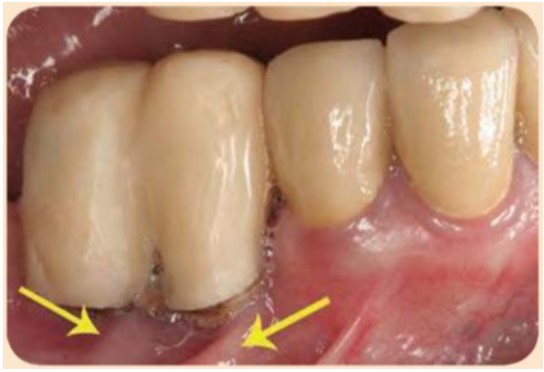

Ngoài ra, trong những trường hợp đặt implant ở sống hàm teo nhiều và thiếu nướu sừng hóa quanh implant, thì khoảng hành lang quanh implant cũng thường bị giới hạn, không đủ chỗ cho dụng cụ vệ sinh răng miệng (ví dụ như bàn chải) làm sạch mảng bám và mảnh vụn thức ăn. Hình dưới đây cho thấy không đủ nước sừng hóa ở mặt ngoài của implant #45 và #46, thiếu ngách hành lang thể hiện qua sự hình thành nếp gấp niêm mạc (mũi tên) quanh khe hở tiếp cận giữa răng #44, implant #45, và implant #46.

Nếp gấp niêm mạc (mũi tên màu vàng) ở niêm mạc xương ở mặt ngoài là dấu vết của khe hở tiếp cận giữa răng #44, implant #45 và implant #46. Nếp gấp niêm mạc cho thấy niêm mạc ổ răng nằm sát với mặt ngoài của phục hình trên implant #45 và #46, gợi ý rằng không đủ khoảng hành lang quanh implant.